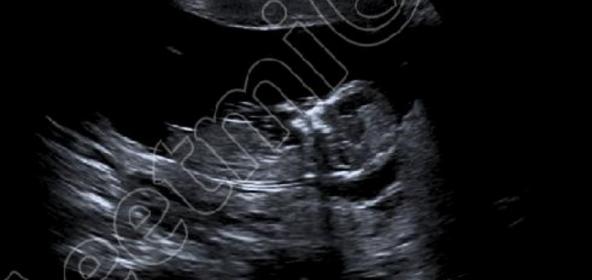

These are more I have. Are they any better?

Yeah they are clearer. Still thinking girl :)

Any more guesses?